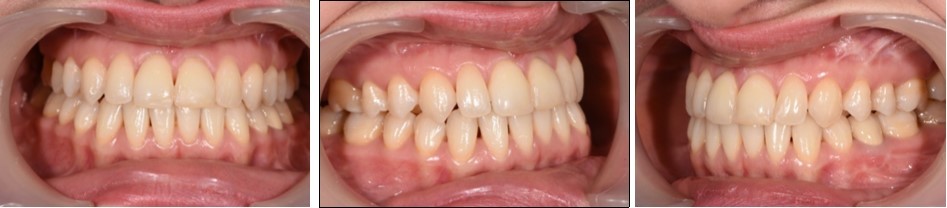

The pre-surgical orthodontic preparation successfully met the following objectives: levelling and aligning, flattening of curbe of Spee, proclination of the lower incisors and elimination of dental compensations. Before surgery, the patient had a normal position of the lower incisors, with IMPA 88 degrees. (Figure 4) Before surgery, a slight anterior open bite and an anterior crossbite could be observed, due to the elimination of dental compensations. Crimpable hooks were placed between each tooth on the 0.019x0.025 SS archwires, to allow placement of intermaxillary elastics after surgery. (Figure 5).

Figure 5.Pre-surgical intraoral photographs

Pre-surgical intraoral photographs